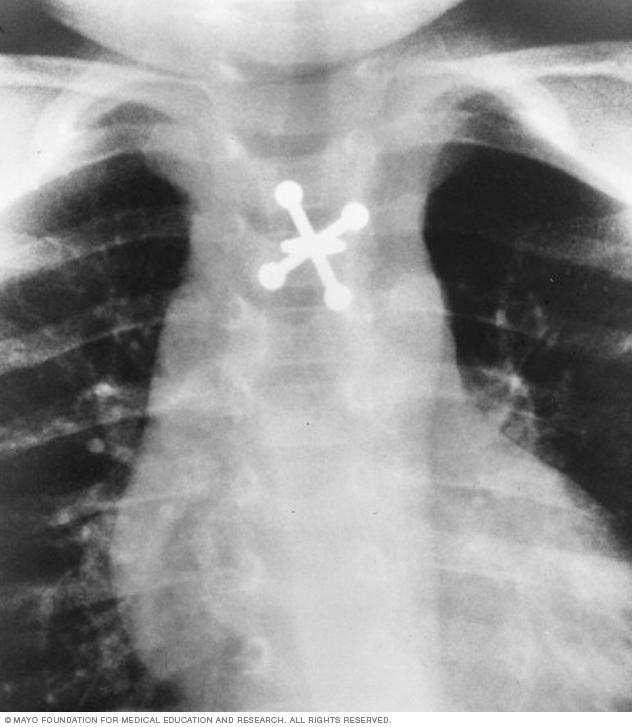

X-ray of swallowed jack

X-rays can locate metal objects your child has swallowed, such as this jack.

• Swallowed items. If a child has swallowed something such as a key or a coin, an X-ray can show the location of that object.